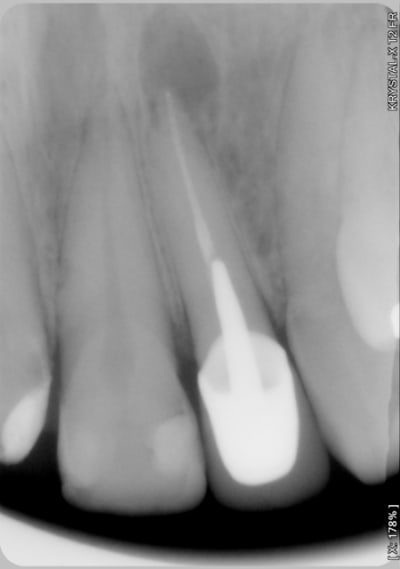

Sourire gingivale a mort, une CCM faite l'année derniere.

Morphotype epais et une bonne bande de gencive keratinisé.

Tout ce dont j'avais besoin pour changer un peu de la "routine" des resections apicales.

Pour la technique c'est le lambeau d'ohsenbein lubke.

Il faut une bonne bande de gencive attaché(5mm), parodonte epais et comme ca t'évite les recession autour des jolies CCM que tu viens de faire.